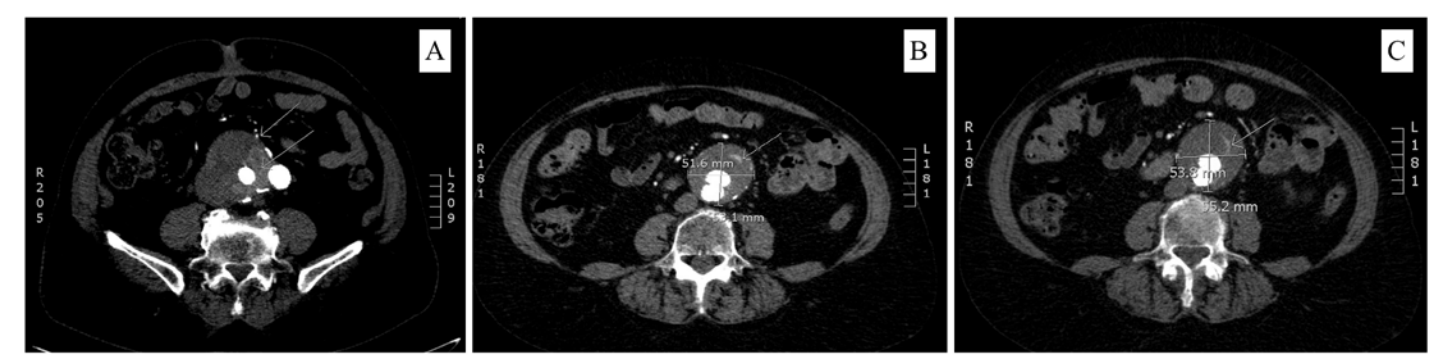

The total incidence of postoperative endoleak was 24.3%, with type II representing 60% of these cases. All other types of endoleak represented an indication for re-intervention (Figure 3, 4). Type II endoleak was an indication for intervention only when sac expansion was detected. We adopted a conservative management approach with a close follow-up strategy with the rest of the cases (Figure 5). This strategy proved safe and effective, with no reported adverse events or ruptures related to this type of endoleak. This is consistent with the Eurostar registry and the report published by Sidloff et al36 after following up on 175 cases of type II endoleak among a cohort of 904 cases of EVAR done in the UK between 1995 and 2013.